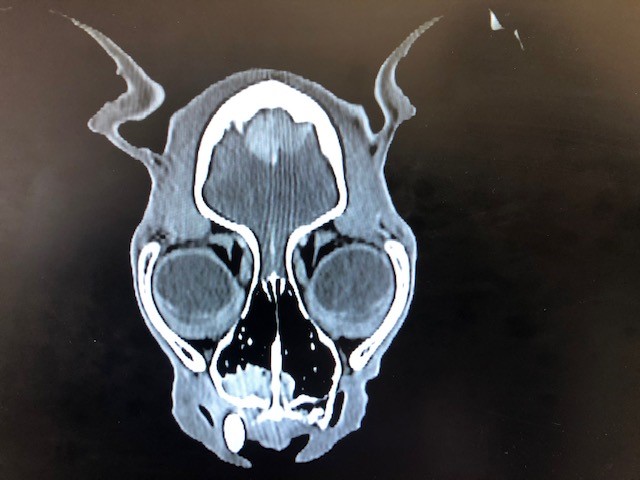

Mein Kater hat leider durch einen Zufallsbefund die Diagnose Hirntumore bekommen. Balou ist 15 Jahre alt und deshalb würde ich mich gegen eine OP entscheiden. Nun habe ich bereits sehr oft gelesen das man alternativ mit Vtalpilzen behandeln könnte.. Mit dem Agaricus Blazei und dem Maitake.